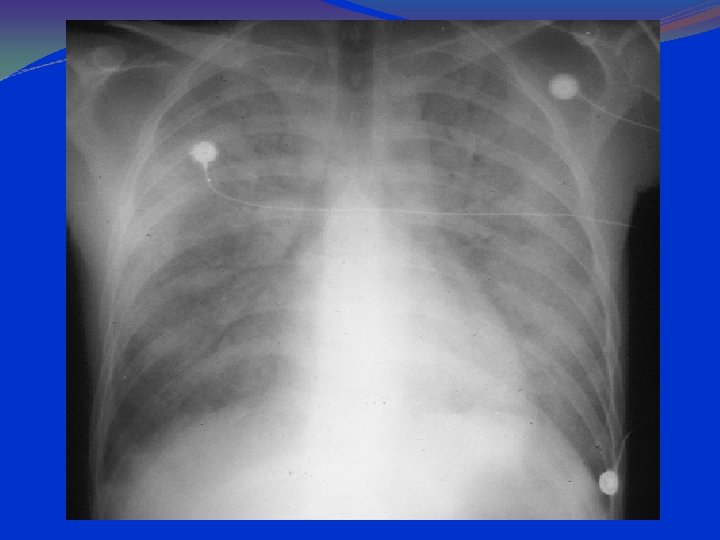

Anteroposterior radiograph of a child with a bacterial pneumonia

parahilar peribronchial infiltrates hilar adenopathy

Tachypnea and fever Diffuse bilateral alveolar disease can be observed by radiography. Diagnosis requires the identification of P carinii in pulmonary tissue or lower airway fluids. Lung biopsy, inducement of sputum, bronchoalveolar lavage, or needle aspiration of the lung. The Gomori, Giemsa, fluorescence-labelled antibody, or toluidine blue O stains may be used to identify the organism.

PCP: CXR Findings 90 -95% have pulmonary infiltrates. Combined interstitial & alveolar infiltrates. Predominantly at bases and centrally. Pneumothorax can be present. Lace like appearance.

PA Chest Radiograph Demonstrates bilateral, perihilar, R > L, ground glass opacities